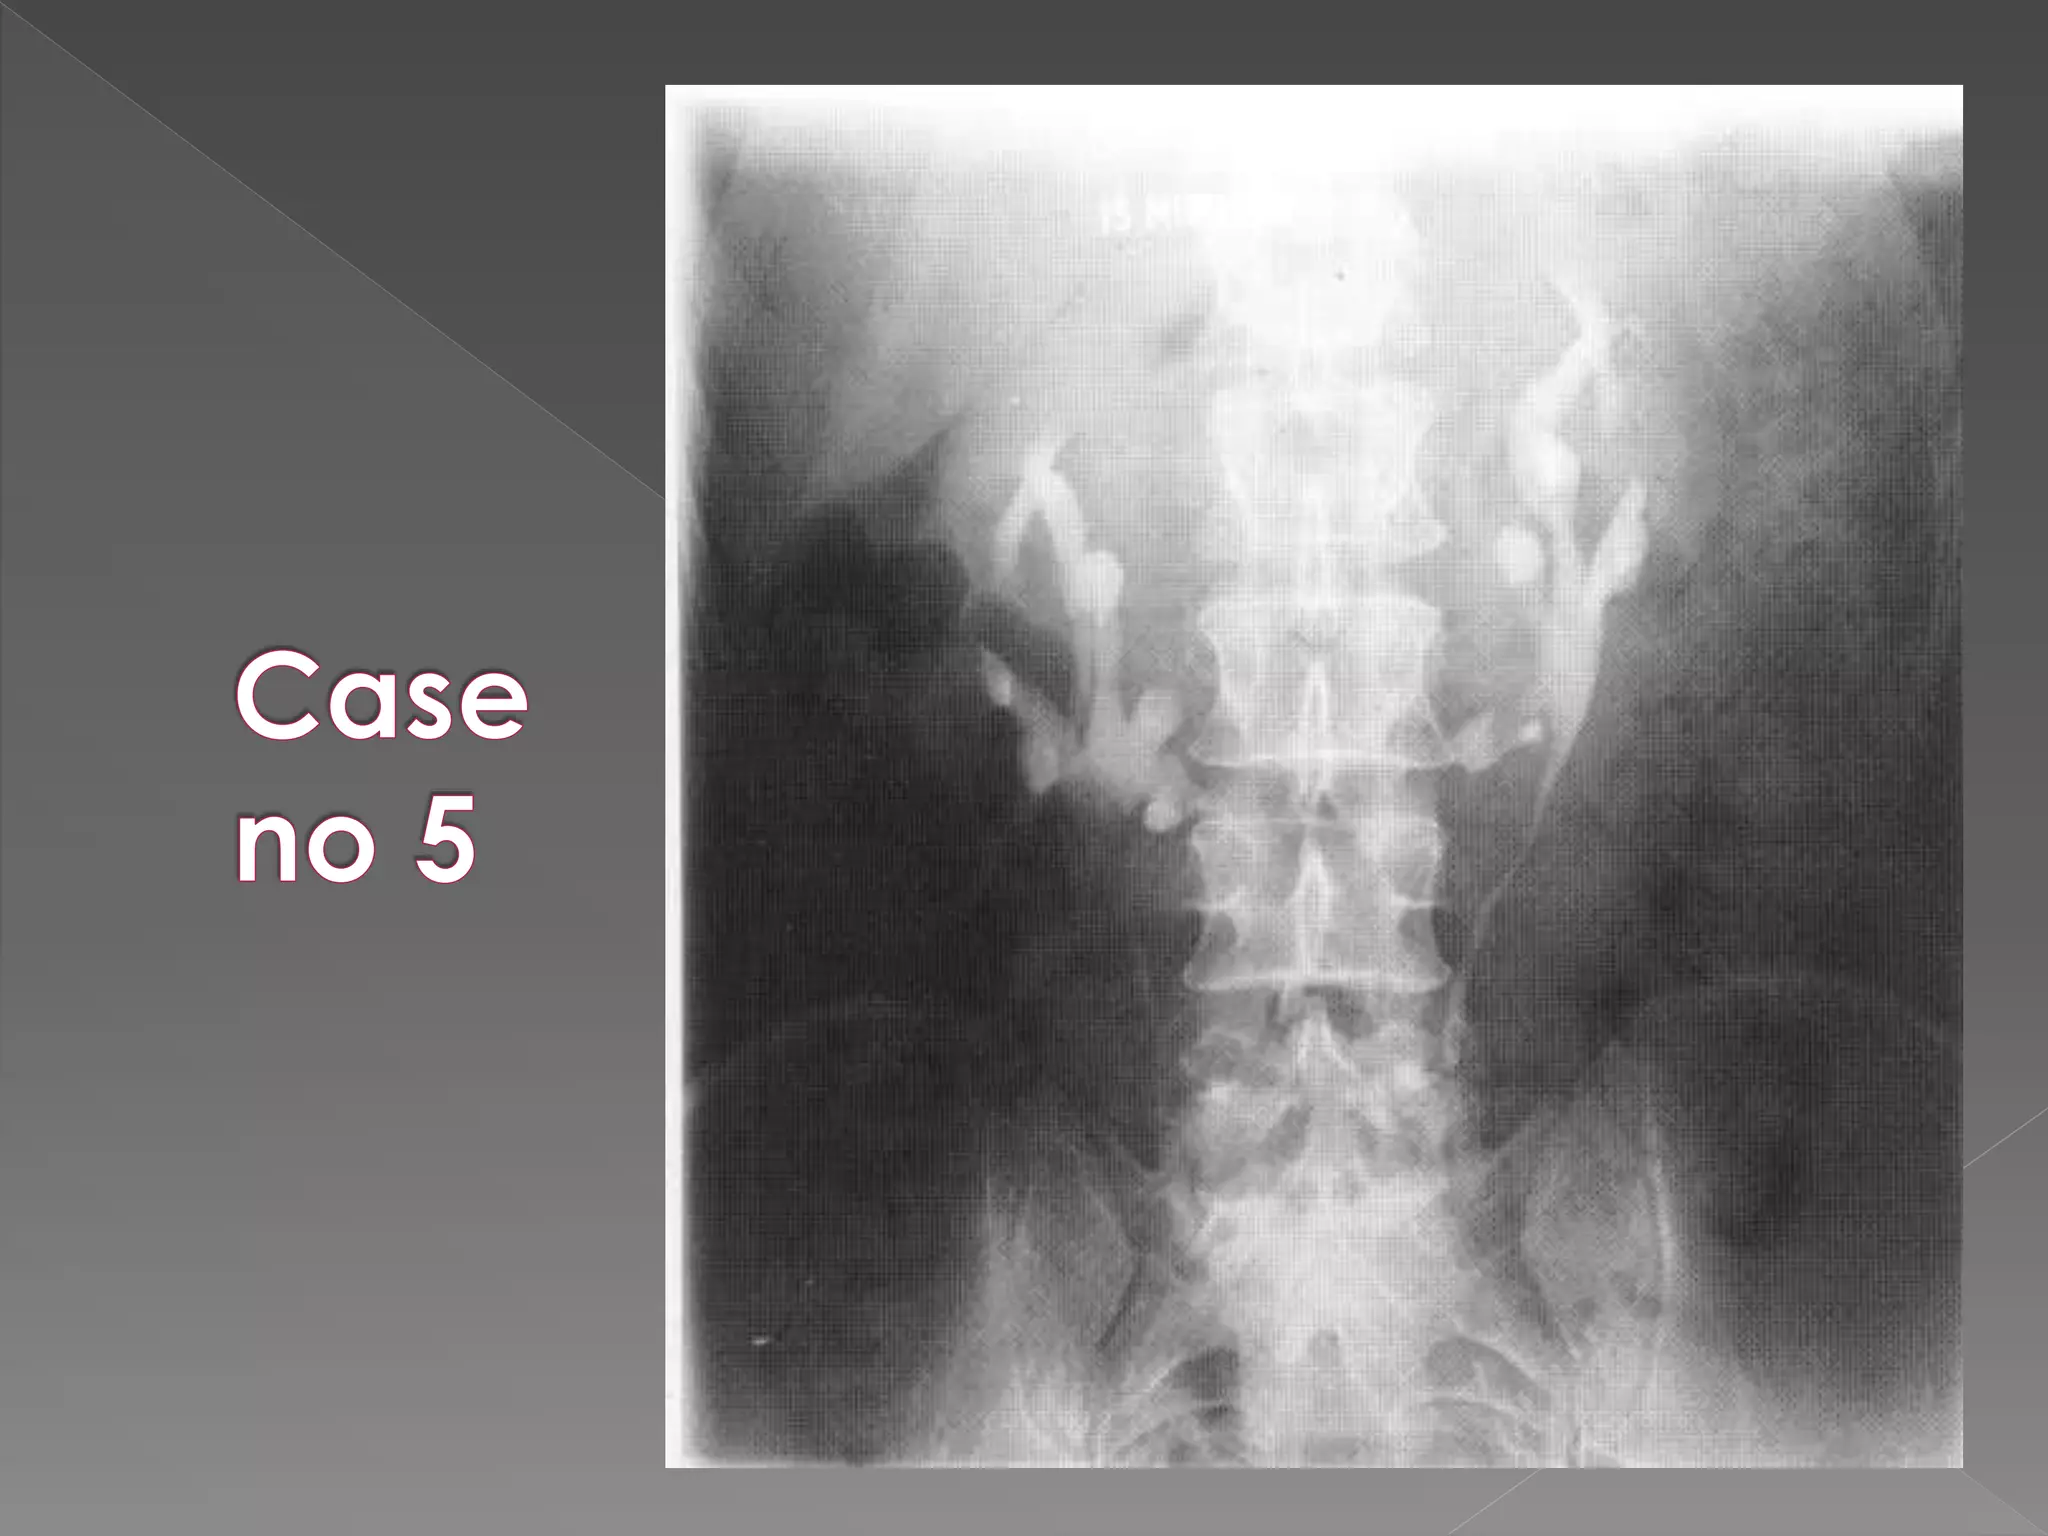

 The plain film demonstrates

calcification within distended

upper pole calyces

 The plainfilm demonstrates calcification within distended upper pole calyces